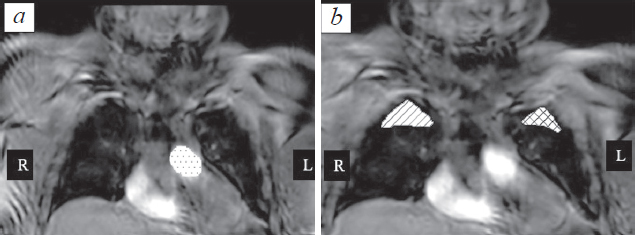

Materials and methods. 10 volunteers with no signs of interstitial lung disease were examined by three-dimensional ultrafast dynamic contrast-enhanced MR imaging using 3D T1-weighted images. The values of pulmonary blood flow (PBF), mean transit time (MTT), and pulmonary blood volume (PBV) for the targeted regions of interest were calculated based on the dynamic image series. For calculations, arterial input function (AIF) was used, as well as the time-intensity curves.

Results. The values of PBF, MTT, and PBV showed statistically significant differences between central and peripheral sections of lungs. Provided model can be implemented for quantitative assessment of regional pulmonary perfusion allows it to be used to determine the reliability of PBF, MTT and PBV values.